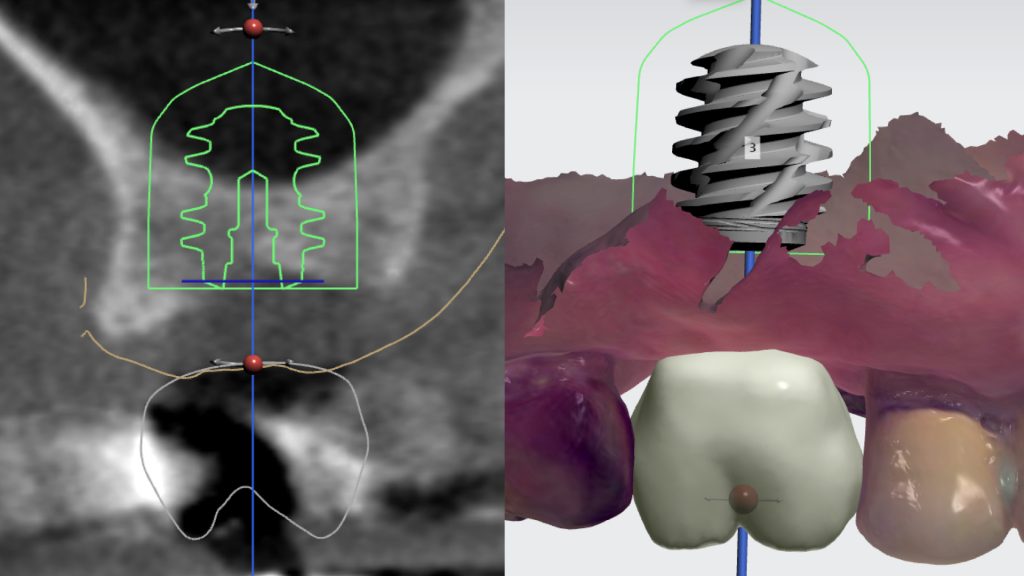

Total Control of Implant Placement Through Digital Workflow

In this video, Dr. H. Ryan Kazemi demonstrates the digital workflow for precise placement of a dental implant.